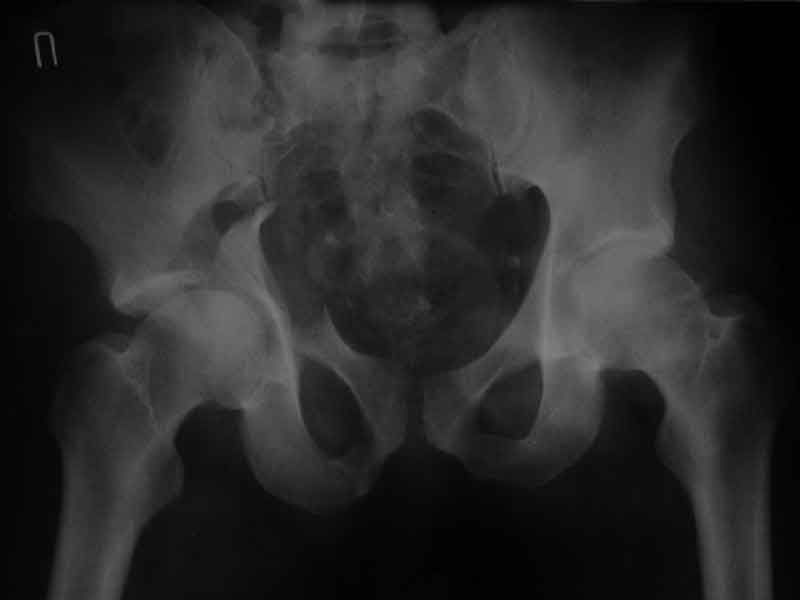

Уважаемые коллеги, нужна помощь, поступил больной с переломом лонной и седалищной кости слева, перелом вертлужной впадины слева, нестабильный вывих левой бедренной кости. Попытки вправить бедренную кость- безуспешны. На данный момент находится на скелетном вытяжении, посоветуйте какую тактику ведения данного больного выбрать оптимально.Спасибо.

Досылаю рентгенограмму

> Досылаю рентгенограмму

Бессмысленно заниматься лечением повреждений вертлужной впадины по такой рентгенограммам, попытайтесь вправить вывих и отправить в лечебное учреждение, где занимаются лечением подобных повреждений.

Поверьте, ни в коем разе не хочу Вас обидеть, но если нет возможности сделать качественные рентгенограммы в нескольких проекциях, то грамотное лечение таких повреждений практически невозможно.